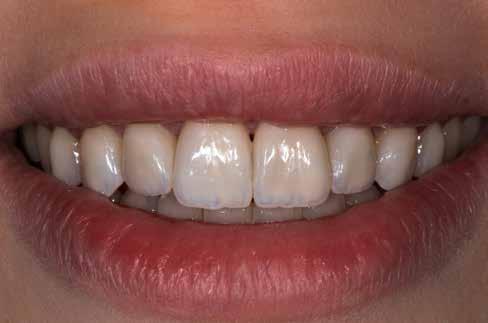

A cikkben egy fiatal nő kezelésének interdiszciplináris megközelítését foglaltuk össze, aki fogászati állapota miatt hoszszú ideje szenvedett fizikálisan és pszichésen is (1. ábra)

1. a–c ábrák: Kiindulási helyzet: fiatal páciens komoly fizikai és pszichés szenvedéssel.